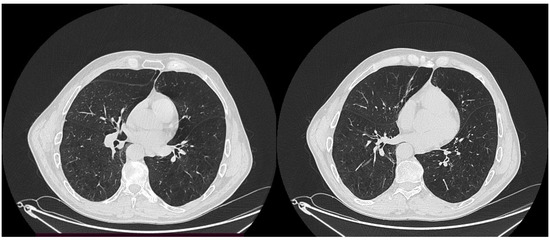

2. Case Report

3.2. Imaging Diagnosis